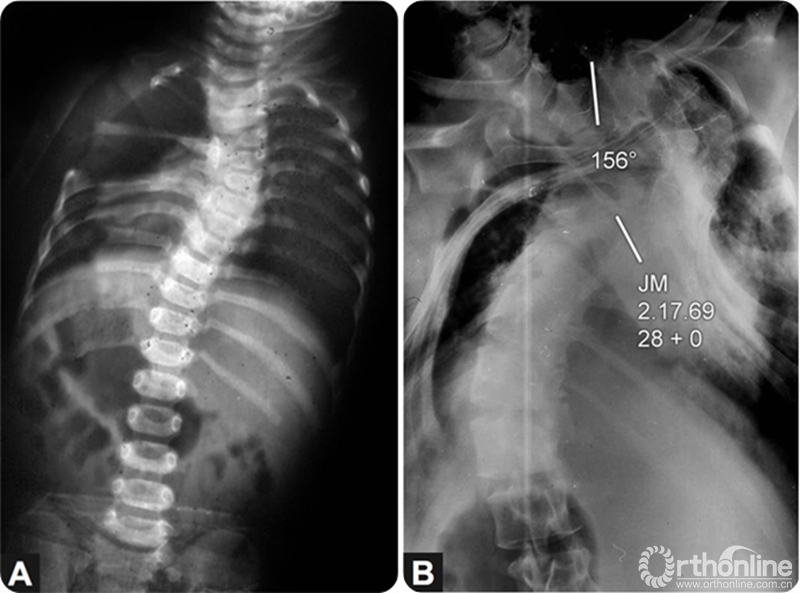

图1:12个月男孩,出生时发现先天性脊柱侧凸,侧凸角度35°;B:该患者未接受任何治疗,到28岁时侧凸角度进展到156°,脊柱胸廓畸形导致严重的限制性肺疾病和呼吸窘迫,患者在拍片1周以后死亡。(Congenital deformities of the spine by Robert B. Winter, Thieme Stratton, New York, 1983)